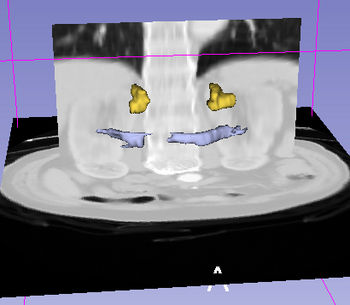

Faceted Visualizer enables a user to create flexible visualizations using Slicer by combining a 3D digital atlas and 3D scene models with an ontology. This visualizer is primarily intended as a learning tool (e.g. neuroanatomy) and allows users to employ "drill-down" search strategies starting from a specific user typed query by showing the related options extracted by searching the ontology. Currently, the faceted visualizer has been tested with the SPL-PNL Brain atlas and the SPL Abdominal atlas and the FMA ontology. The Radlex ontology is currently not supported by the visualizer.

The faceted visualizer integrates an ontology with a 3D Atlas for combined visualization with relevant textual information extracted from the ontology. The visualizer module employs a hierarchical search on the ontology to obtain the visualizations. The visualizer supports simple (e.g. "putamen", "motor system", etc), to complex queries ("liver;arterial supply + stomach + kidney;arterial supply").

The Query Results panel shows the result of a query, consisting of all the associated predicates and parts for the query. The Figure User Page GUI shows the result of a simple query "limbic system".Additionally, the interface also shows a Comment that contains any relevant textual information about the query obtained from the ontology. The user can refine a search by selecting from the query result. Optionally, the user can also select by clicking on any selection from the Query History or Favorite Queries panel to redo search and visualization. The interface supports the multiple selections to form complex queries. The visualization resulting by searching with the query "Limbic system" is shown below.